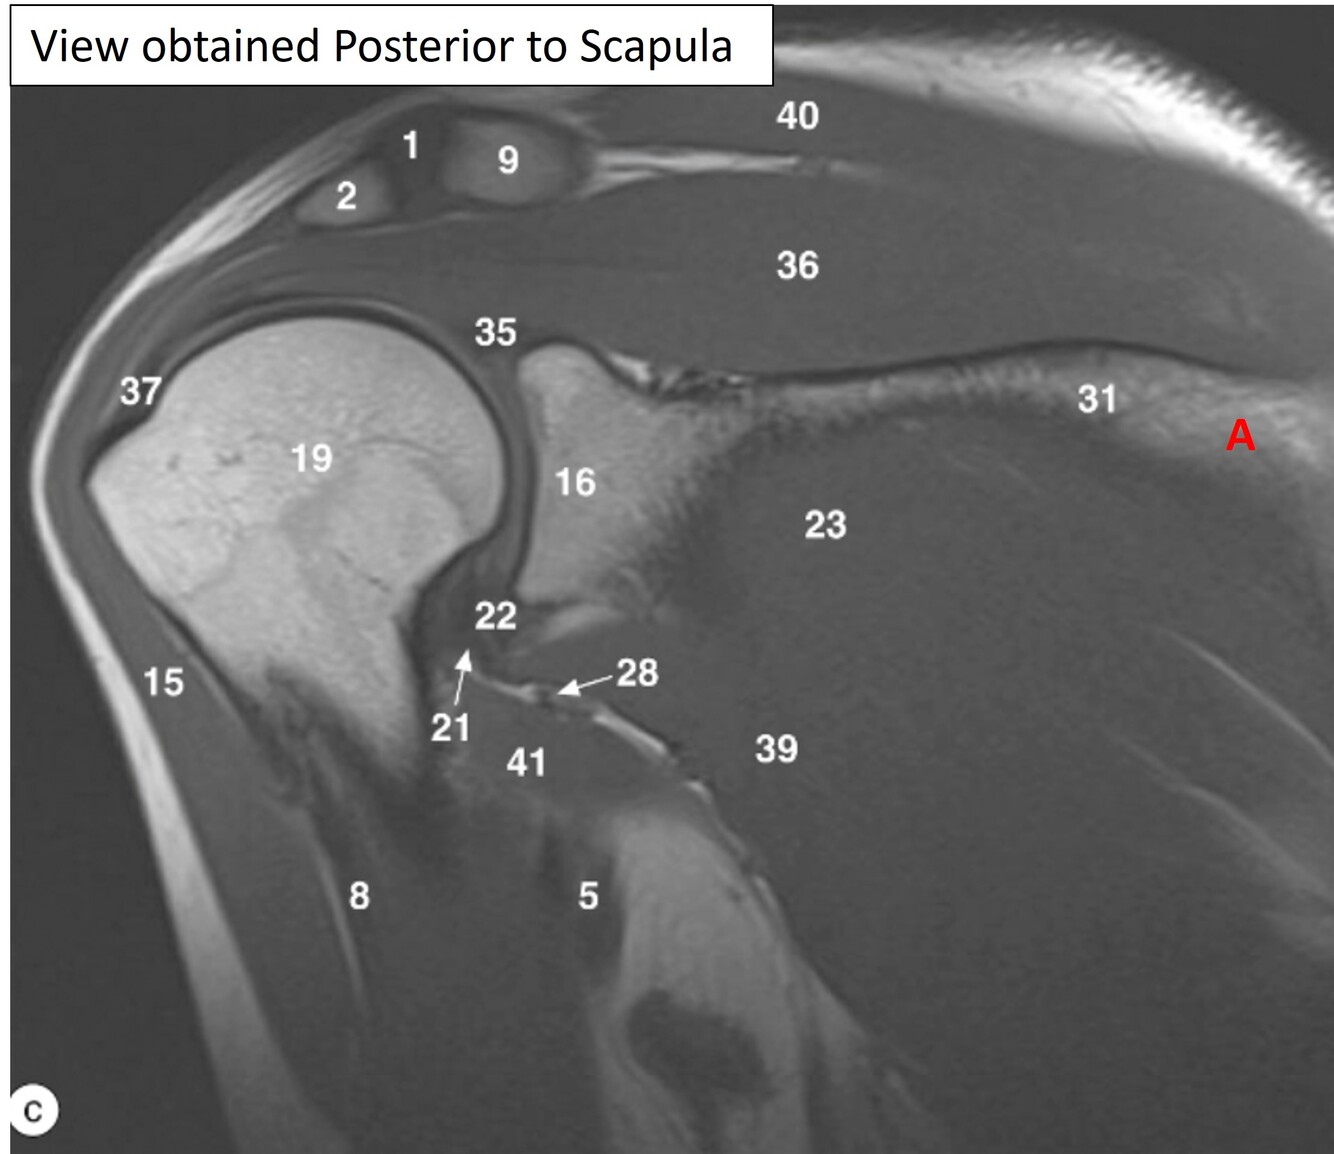

7

Q

Label a

A

Supraspinous fossa